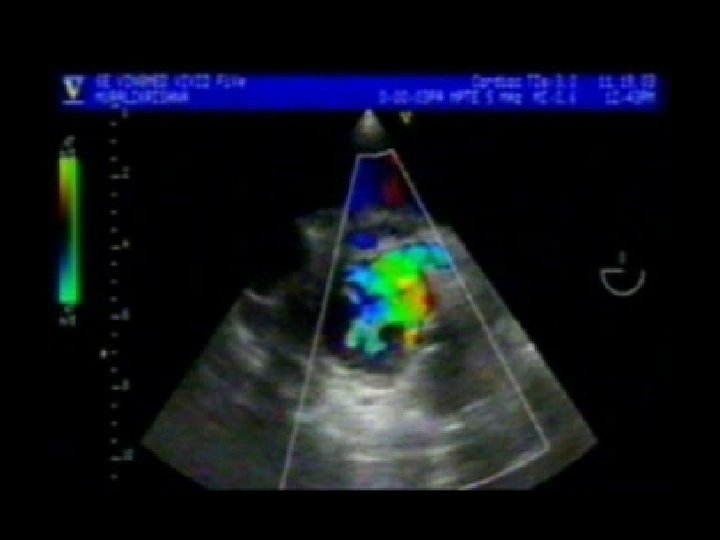

NJ F 30/Y MVR SOB PND Palpitation Afebrile MVR ; PROSTHETIC DEHISCENCE SEVERE PARA PROSTHETIC MR